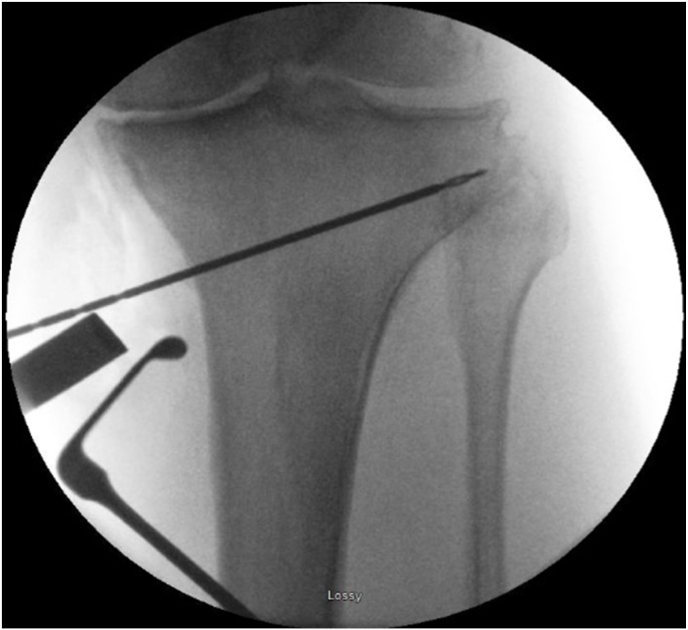

Fig. 4.

Positioning of drill tipped wire to determine the line of the osteotomy, the tip of the wire is at the level of the fibula head.